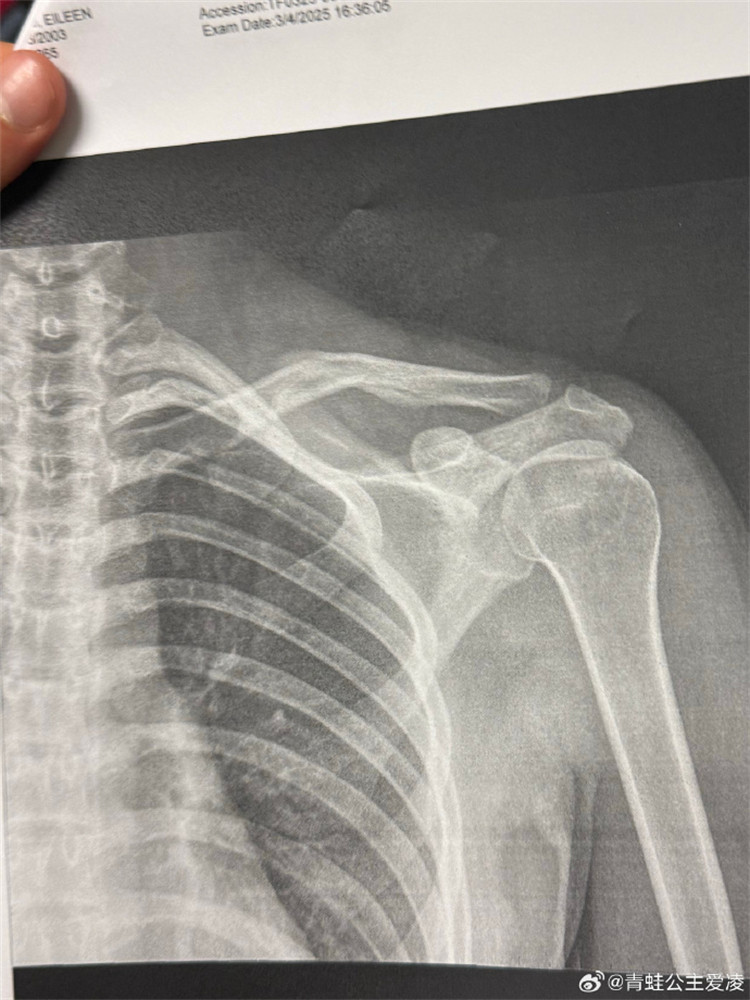

今年3月9日,谷愛凌在社交媒體曬出肩部骨折的X光照片,並配上一個心碎的表情,隨後相關話題登上熱搜。